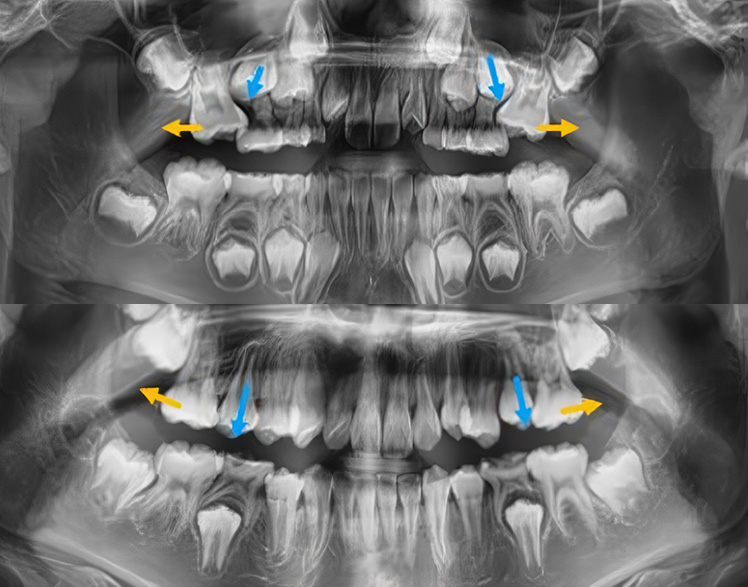

Impacted Tooth

숨어있는 치아교정,

매복치

매복치아나 늦게 나오는 치아 때문에 걱정되시나요?

교정치료를 통해 숨어있는 치아가 자연스럽게 나올 수 있도록 도와드립니다.

아이의 건강한 치아 배열을 위해 적절한 시기에 시작하세요.